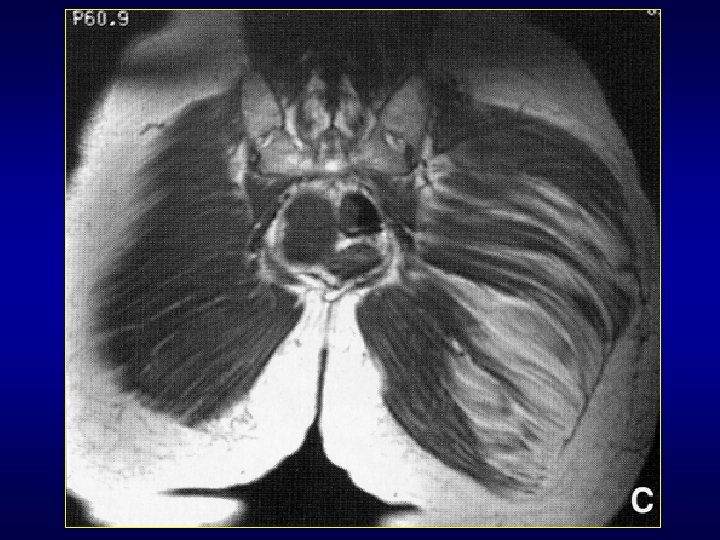

Myopathies inflammatoires • On distingue les polymyosites, les dermatomyosites, les myosites à inclusion • Atteinte inflammatoire dysimmunitaire des muscles striés • Diagnostic par clinique, CPK, EMG, biopsie d’un muscle proximal • Sémiologie IRM: inflammation, atrophie, infiltration graisseuse. Oriente biopsie

Chef court M. biceps Myosite focale inaugurale d’une polymyosite